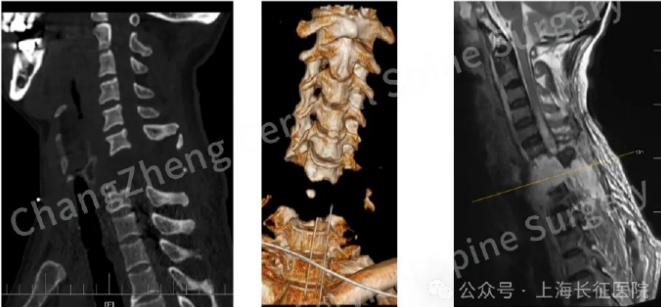

患者李某因颈部遭受机械臂重击,导致颈椎瞬间遭受毁灭性损伤,当场高位截瘫、心跳骤停,经紧急心肺复苏才勉强恢复微弱生命体征。

影像学检查结果显示:颈椎发生极其罕见的大跨度脱位,其严重程度犹如“身首离断”,已造成脊髓严重挫伤、关键神经血管结构撕裂,骨折脱位区域形成巨大血肿,双侧椎动脉均因损伤而闭塞。

经过三小时的手术,最终精准地将完全离断错位的颈椎结构完美复位。

术后,患者意识状态迅速恢复清晰,成功拔除了气管插管,在家人辅助下坐起,标志着其神经功能开始出现积极信号,现已转入系统康复阶段。